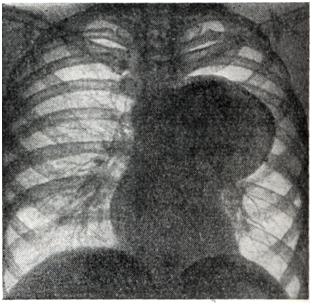

Аневризмы восходящей аорты обычно хорошо определяются в виде выпячиваний на правом контуре сосудистой тени в прямой проекции (рис. 3) и на переднем контуре — в левом косом и боковом положениях. Гораздо реже аневризма располагается на левой стенке восходящей аорты и образует выпячивание слева. Аневризмы дуги аорты (рис. 4) в прямой проекции обычно имеют вид массивной тени над изображением сердца, а в левом переднем косом положении проецируются на область дуги аорты. Аневризмы нисходящей аорты дают добавочные тени по левому контуру сосудистой тени (книзу от первой дуги) в прямой проекции и проецируются на ретрокардиальное пространство и тень позвоночника в косых положениях. Бывают множественные аневризмы аорты. Дифференциальный диагноз аневризмы аорты с опухолями и кистами средостения представляет большие трудности. Признак пульсации имеет лишь ограниченное значение: она может быть передаточной при опухолях и отсутствовать при тромбированной аневризме или сращениях. Рекомендуется применение томографии и пневмомедиастинографии. Кроме обычно встречающихся вторичных признаков — смещения пищевода и трахеи, возможна картина ателектаза легкого вследствие сдавления бронха, высокое положение диафрагмы из-за давления на диафрагмальный нерв, обеднение кровотока в легком ввиду сдавления легочного ствола, атрофия от давления тел позвонков, ребер (рис. 5). Рентгенологическое распознавание аневризмы брюшной аорты по обычным снимкам возможно лишь при наличии обызвествления стенок аорты или типичной деструкции тел позвонков. В предоперационном диагнозе всех аневризм аорты решающее значение имеет аортография.